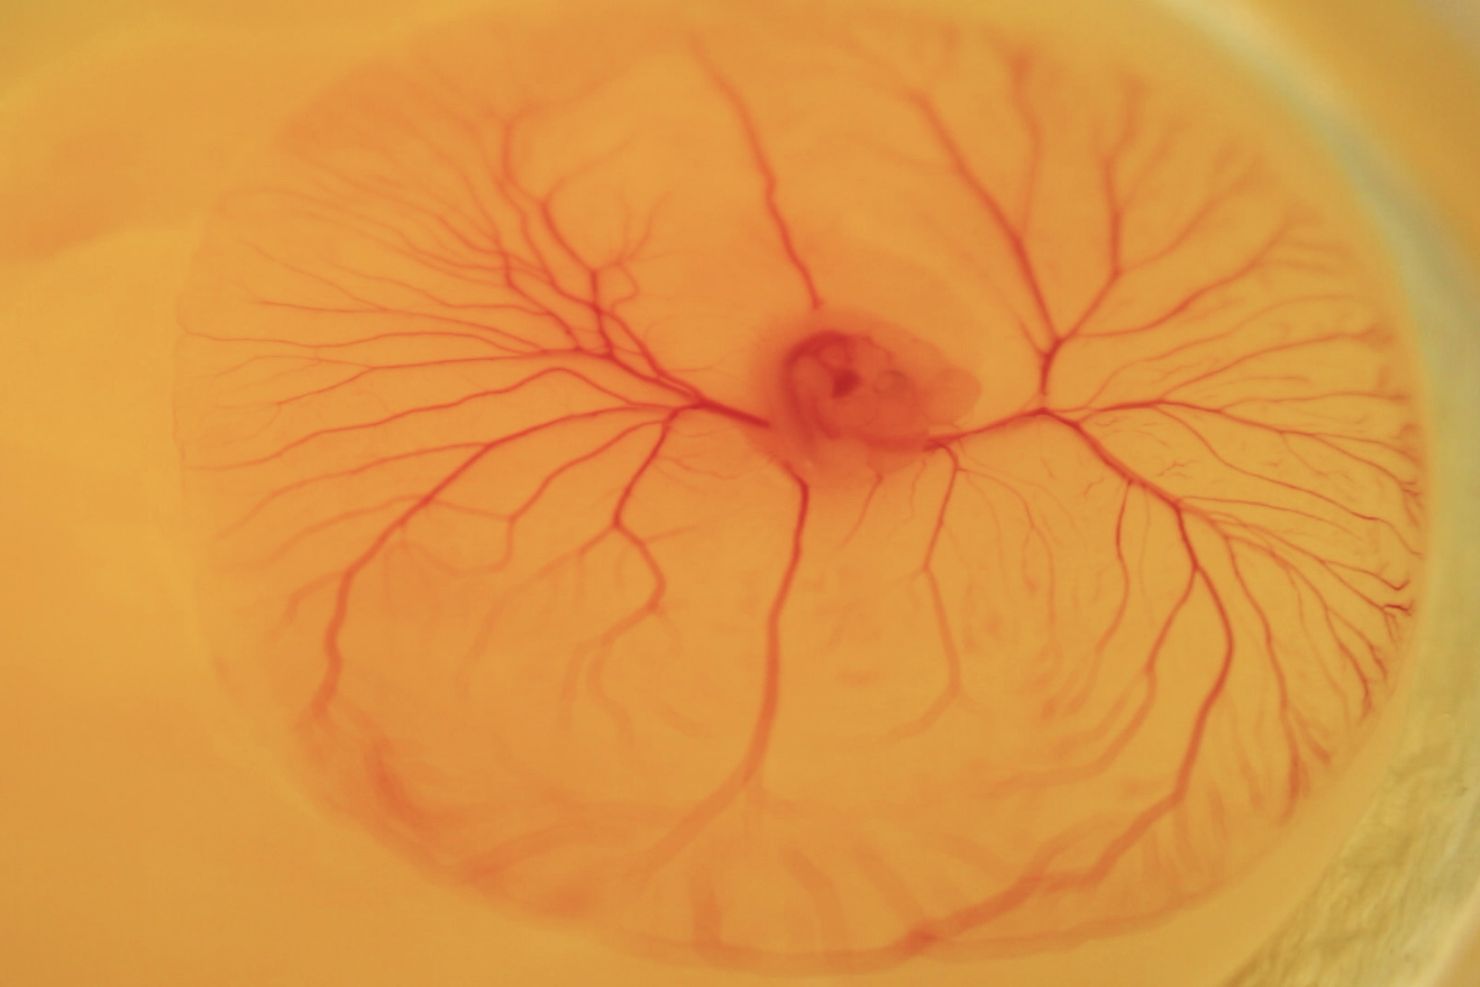

In diesem Jahr geht der Felix-Wankel-Tierschutz-­Forschungspreis an das Studienteam um ­Prof. Dr. Christine Baumgartner mit Privatdozent Dr. ­Thomas Fenzl und Prof. Dr. Benjamin Schusser von der Technischen Universität München (TUM). In ihrer Studie „Tierschutz für das Ei – Untersuchung zur Entwicklung der Nozizeption und des Schmerz­empfindens beim Hühnerembryo“ untersuchten die Forschenden kardiovaskuläre, neurophysiologische und verhaltensbasierte Reaktionen von Hühner­embryonen, um ­herauszufinden, ab wann diese die Fähigkeit zur Nozizeption ent­wickeln bzw. Schmerz empfinden können. Die Ergebnisse zeigten, dass Hühnerembryonen ab dem 13. Bruttag eine physiologische, neuronale Gehirnaktivität haben und ab dem 15. Bruttag deutliche ­Reaktionen auf schmerzhafte Reize messbar sind. „Als ­Forschende sehen wir uns in der Verantwortung, den Tierschutz und das Tierwohl durch interdisziplinäres und innovatives Denken und Handeln immer weiter voranzubringen“, so Baumgartner. Die Forschungsergebnisse hatten ­direkten Einfluss auf die Tierschutz-Gesetz­gebung: Seit Januar 2024 ist das Töten von Hühnerembryonen im Rahmen der Geschlechtsbestimmung im Ei ab dem 13. Bruttag in Deutschland verboten.